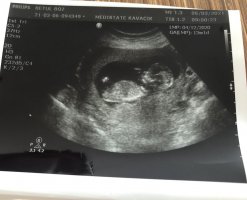

merhaba ramzi teorsine göre yorumlayabilirmisiniz, 8+1 günlük görüntü

Çok net görememekle birlikte sanki kız gibi gördüm emin değilim ama sadmin adminim yorumlarsa daha iyi olur sanıyorum. Bana göre kız gibi geldi net değilim🙂 cinsiyeti öğrendikten sonra da bize yazarsanız seviniriz sağlıkla alın kucağınıza:hamis: